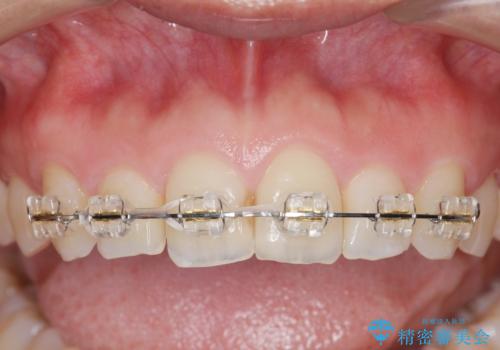

出っ歯に見える前歯の改善 部分ワイヤーとマウスピース矯正

- 出っ歯に見える前歯の改善を希望され、来院されました。

マウスピースでは改善の難しい歯の動きを部分ワイヤー矯正で整えたのち、奥歯の噛み合わせや細かい歯の並びをマウスピース矯正インビザラインで整えていきます。

最終的な前歯の並びに大変満足いただくことができました。